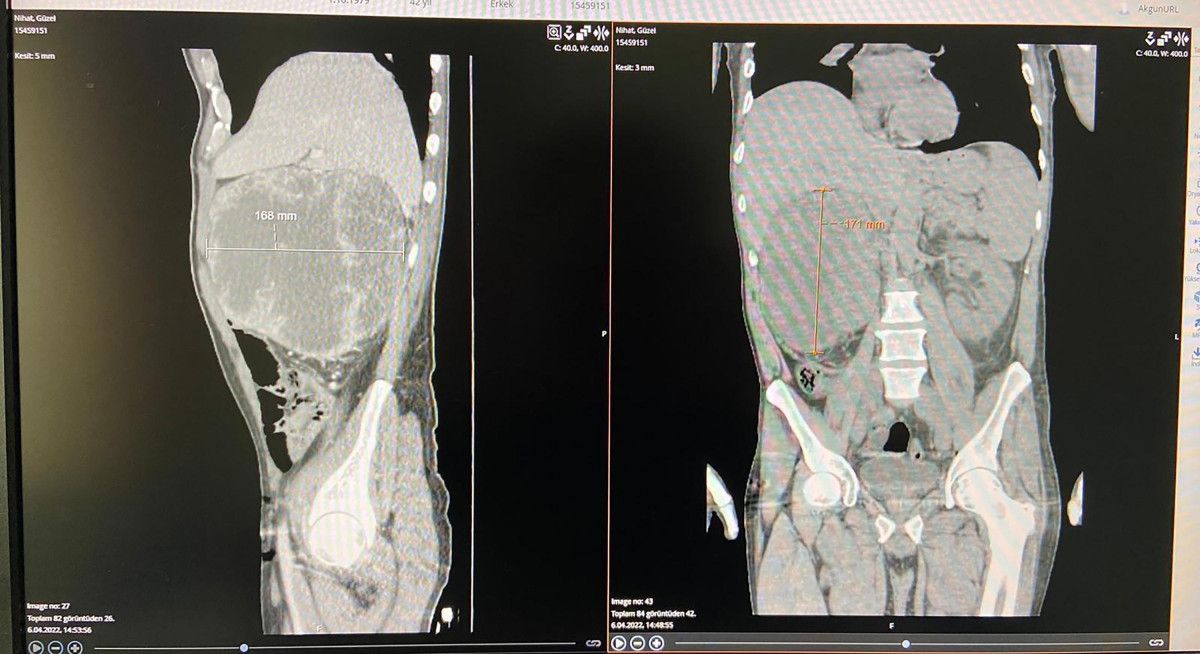

Ürolog operatör Dr. Fatih Akkaş’ın yaptığı muayenede sağ yumurtalığında şişlik belirlenen Güzel'in çekilen ultrason ve filmlerinde karnında 20 santimlik kitle olduğu tespit edildi. Böbrek, karaciğer, damarlara yapışık olan kitlenin çıkarılması için Güzel, ameliyata alındı.

Nihat Güzel'in ilk muayenesinde sağ yumurtalığında şişlik belirlediklerini anlatan Dr. Akkaş, "Sağ taraftaki şişlik bizim aklımıza karın içerisinde baskı yapan kitle olabileceğini getirdi. Yapılan tetkiklerde ve çekilen filmlerde sağ tarafta 20 santimetre boyutunda bir kitle tespit edildi. Böbrek, karaciğer, büyük damarlar ile atardamara yapışık olan kitlenin vücuda yayılmadığını belirledik ve operasyonla çıkarılabileceğini gördük.

Gerekli hazırlıklardan sonra yapılan ameliyatla kitleyi çıkardık. 20 santim büyüklüğündeki kitle, biraz daha geç kalınsaydı vücuda yayılma ihtimali vardı. Komşu dokular karaciğer, böbrek ve bağırsaklara zarar vereceği için belki çıkarmak güç olacaktı. 2-3 ay geç kalınsaydı işimiz daha zor olacaktı" ifadelerini kullandı.